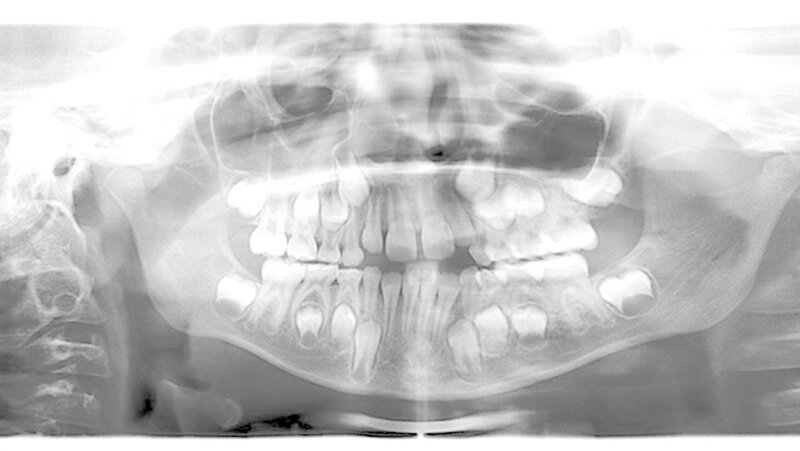

Endo: (Kontra-)Indikation im Milchgebiss

Die Erfolgsrate endodontischer Behandlungsmaßnahmen im Milchgebiss ist dann hoch, wenn die (Kontra-)Indikation korrekt gestellt wird. Als häufigstes Verfahren kommt die Caries-profunda-Therapie zum Einsatz, berichtet Prof. Roswitha Heinrich-Weltzien (Jena) und Prof. Jan Kühnisch (München) aktuell in der Zeitschrift "Oralprophylaxe & Kinderzahnheilkunde". Diese Therapie zielt auf die Vitalerhaltung der klinisch symptomlosen Pulpa ab.

Mit der selektiven Kariesexkavation stehe zudem eine schonenede Herangehensweise zur Verfügung, die vielen Herausforderungen in der Behandlung des kindlichen Patienten gerecht wird. Im Fall der Pulpabeteiligung sei die Pulpotomie insbesondere an Milchmolaren indiziert.

Die Pulpektomie und Wurzelkanalfüllung werde am häufigsten an Milchfrontzähnen bei Kindern mit frühkindlicher Karies praktiziert. Für die zeitige Sicherung des Therapieerfolgs nach einer endodontologischen Behandlung ist die Einbeziehung der Patienten in ein alters- und risikoadäquates Recall- und Präventionsprogramm eine unabdingbare Voraussetzung, betont die Autorin.